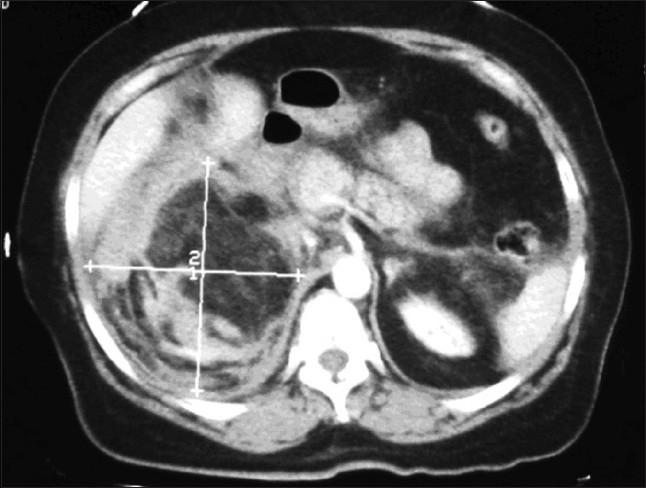

We report a case of Wunderlich's syndrome in an obese woman associated with massive retroperitoneal hemorrhage. Stable hemodynamic patient condition was obtained by selective arterial embolization. Since the first embolization of a renal angiomyolipoma in 1976 by Moorhead et al., highly selective renal arterial embolization of angiomyolipoma with rupture has become a procedure that offers greater efficacy, particularly in life-threatening cases.

我们报告一例肥胖女性的肾血管平滑肌脂肪瘤破裂综合征伴大量腹膜后出血。通过选择性动脉栓塞使患者血流动力学状况稳定。自1976年Moorhead等人首次对肾血管平滑肌脂肪瘤进行栓塞以来,对破裂的肾血管平滑肌脂肪瘤进行高选择性肾动脉栓塞已成为一种疗效更佳的治疗方法,尤其是在危及生命的病例中。